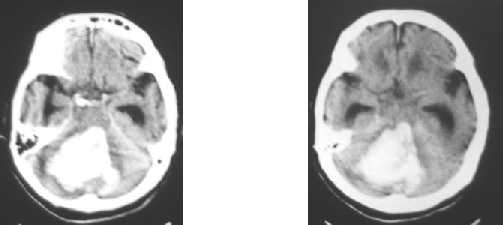

Nontraumatic ICH : cerebellar